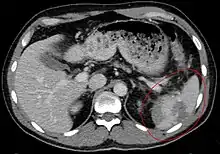

| Spleen ruptured by trauma | |

Splenic rupture is usually evaluated by FAST ultrasound of the abdomen.[4] Generally this is not specific to splenic injury; however, it is useful to determine the presence of free floating blood in the peritoneum.[4] A diagnostic peritoneal lavage, while not ideal, may be used to evaluate the presence of internal bleeding a person who is hemodynamically unstable.[5] The FAST exam typically serves to evaluate the need to perform a CT scan.[5] Computed tomography with IV contrast is the preferred imaging study as it can provide high quality images of the full peritoneal cavity.[4]